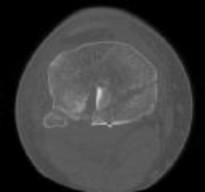

**CLINICAL SITUATION**

Figures 1 and 2 are the radiographs of a 35-year-old man who is brought into the emergency department after a motor vehicle collision. He is complaining of isolated knee pain. Examination reveals swelling, blood filled blisters, popliteal ecchymosis, joint line pain, and limited knee joint motion. His pulses and sensation are normal.

Figures 3 through 8 are the axial and sagittal CT scan sections of the injury. Intra-operative patient positioning for definitive fixation should be